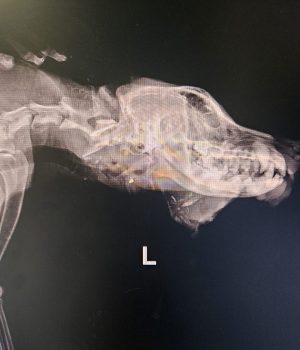

Seine Verletzungen waren schwer: mehrere Brüche der hinteren Gliedmaßen, schlechte Blutwerte und massive Verletzungen im Gesichtsbereich.

Inzwischen hat er zwei schwere Operationen an den hinteren Beinen sowie eine aufwendige Gesichtsrekonstruktion erstaunlich gut überstanden.

Der Kiefer selbst war glücklicherweise intakt. 🙏